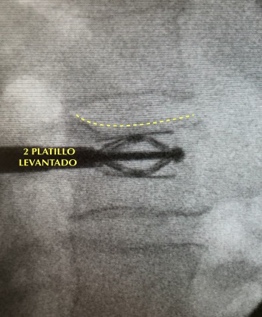

La técnica consiste en rellenar la vértebra rota con un cemento acrílico. Habitualmente se hace con sedación y en régimen ambulatorio. Las heridas en la piel son de 1 cm. Los trócares se meten dentro de la vértebra a través de los pedículos, evitando lesionar los nervios y/o la médula. Una vez dentro del cuerpo vertebral, se inyecta el cemento en cantidad suficiente para rellenar la vértebra rota. Esto se consigue gracias un aparato de Rx escopia y al medio de contraste que va mezclado con el cemento.

La vertebroplastia consiste en rellenar el cuerpo vertebral con cemento directamente a través de los trócares (Fig 1 y Fig 2).

La cifoplastia es lo mismo, pero con un paso previo, consistente en generar un hueco o cavidad dentro de la vértebra fracturada. Este hueco se hace con un balón, globo o dispositivo (similar al gato para levantar un coche con la rueda pinchada), que una vez dentro de la vértebra, se hinchará o expandirá para tratar de levantar la vértebra aplastada o generar dicho hueco, que posteriormente albergará el cemento (Fig 3).